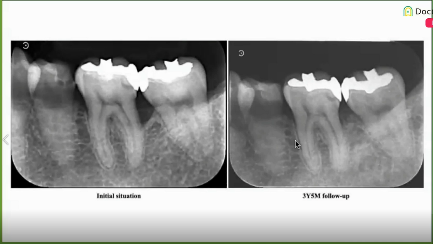

セミナーの後半では「サイトランス グラニュール」を使用した歯周組織再生療法の臨床症例について解説いただきました。

歯周組織再生療法の分類別に症例を供覧し、各症例で使用した材料や手技についても丁寧に解説いただきました。材料に関しては、多くの先生方から注目されている、成長因子や骨補填材料の特性について解説いただきました。その他に縫合や歯周組織再生療法による治療の流れの解説もあり、より臨床に則したセミナーになりました。